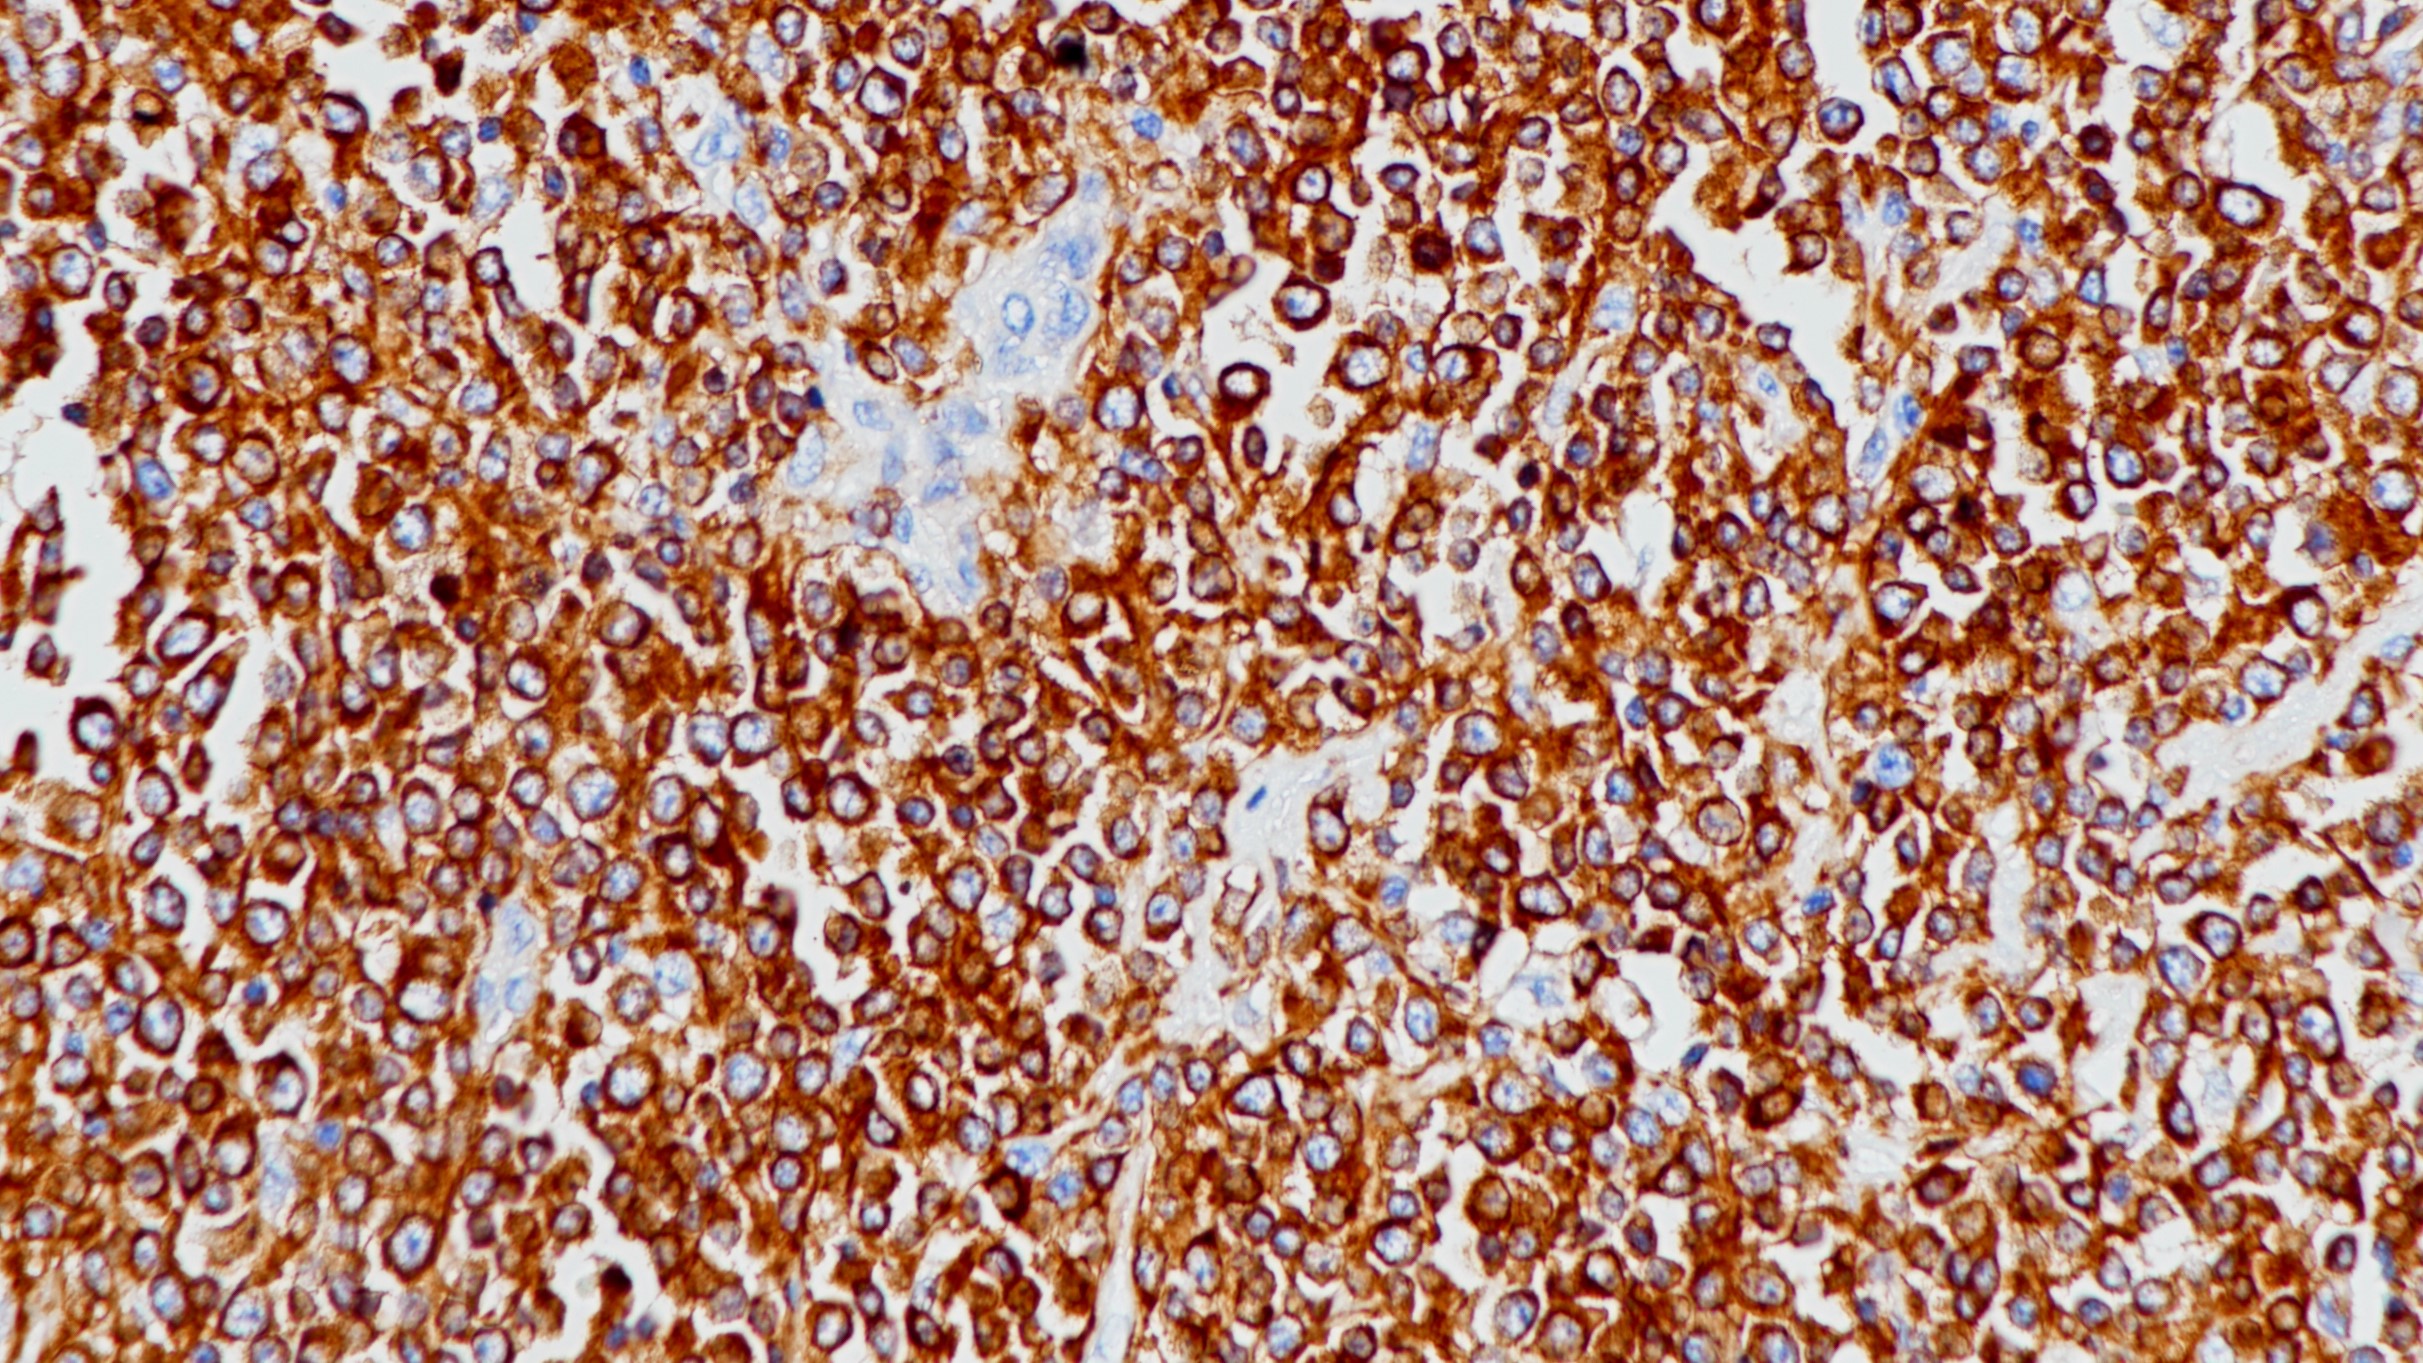

1. Overexpression of the β Subunit of Human Chorionic Gonadotropin Promotes the Transformation of Human Ovarian Epithelial Cells and Ovarian Tumorigenesis [J] . Xiaoqing Guo,Guangzhi Liu,Isaiah G.

Schauer,Gong Yang,Imelda Mercado-Uribe,Fan Yang,Shiwu Zhang,Yuanli He,Jinsong Liu. The American Journal of Pathology . 2011 (3)